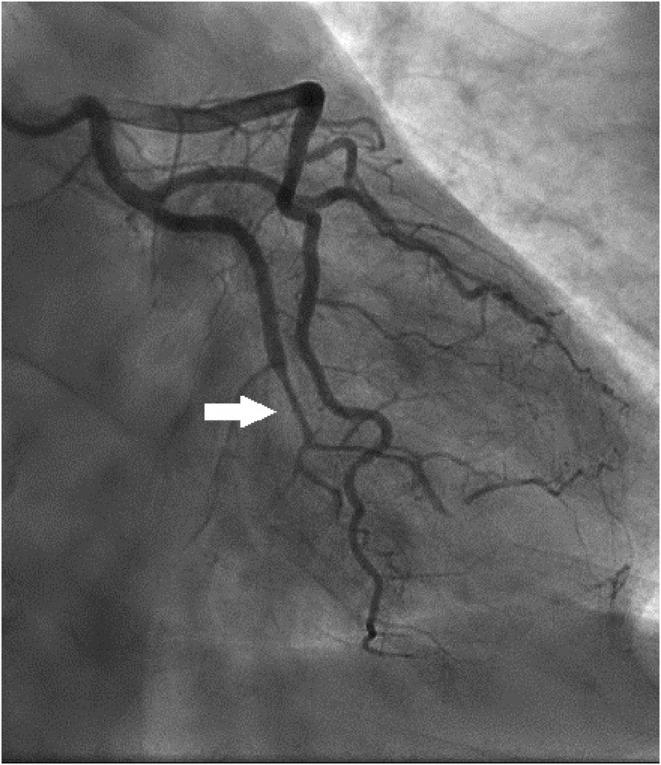

We report a spontaneous coronary artery dissection (SCAD) case in a lady with a history of recent COVID-19 and without any known predisposing factors. We also highlight the value of CMR as a noninvasive tool for tissue characterization, which can also be more applicable during the COVID-19 pandemic.

我们报告了一例近期有新冠病毒疾病(COVID-19)病史且无任何已知易感因素的女性自发性冠状动脉夹层(SCAD)病例。我们还强调了心脏磁共振成像(CMR)作为一种用于组织特征描述的非侵入性工具的价值,在新冠病毒疾病大流行期间它可能更适用。